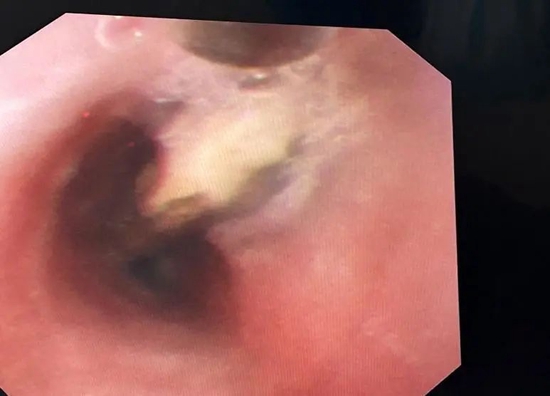

一切准备就绪后,马莲美主任医师持镜探查气道,发现一颗大大的瓜子在左主支气管开口处和主气道中随着呼吸运动上下飘动,若瓜子再次返回声门下,童童随时会有窒息缺氧的风险。由于异物体积大,且经过气道分泌物的浸泡,表面光滑不易抓取,加之受限于局部麻醉的因素,反复网篮套取及活检钳钳取均难以取出。遂与家属积极沟通后急症联系手术室行喉罩下全麻异物取出术。

在儿童呼吸科、呼吸内科、麻醉科、手术室及PICU等多学科协作下,通过不懈努力,最终将异物顺利取出。为一粒约2.4cm×1.1cm×0.7cm大小的带壳葵花籽。异物取出后,大家悬着的心终于放了下来,童童父亲及姑姑激动得泪流满面,感激之情无以言表。看到童童欢快的笑脸,医务人员如释重负。